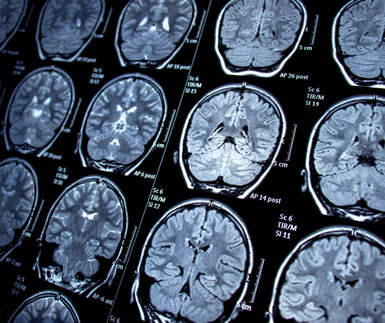

MRI scans of the brain

Magnetic resonance imaging (MRI) is a medical imaging technique that uses radio waves and large magnetic fields to create anatomical images to support the diagnosis of various diseases such as cancer.

However, MRI scans are not easily available across all of Europe due to their size and cost. ‘Low-field MRI’ can be used with portable scanners that could help bridge these supply gaps, however this method currently lacks metrological traceability.

The Partnership project Affordable low-field MRI reference system (22HLT02, A4IM) is working on developing an open-source, fully-characterised, traceable low-field MRI system that is portable and low-cost to increase accessibility of MRI scans across Europe and globally.